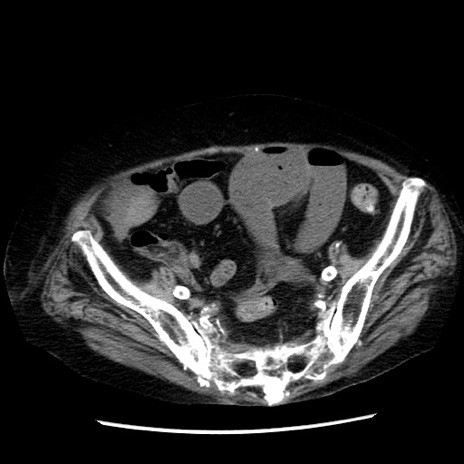

症例14(横断像)

【症例】 90歳代女性

【主訴】 腹痛・嘔吐

【現病歴】今朝から左側腹部痛を認めた。 経過観察していたが、嘔吐を認めたため来院。

【既往歴】 子宮癌術後

【身体所見】 意識清明、BP 127/54mmHg、P 98bpm Sp02 95%(RA)、BT 35.8°C、腹部平坦・軟腸ぜん動音聴取良好、右下腹部圧痛(+) 反跳痛なし

【データ】WBC 9800、CRP 0.46